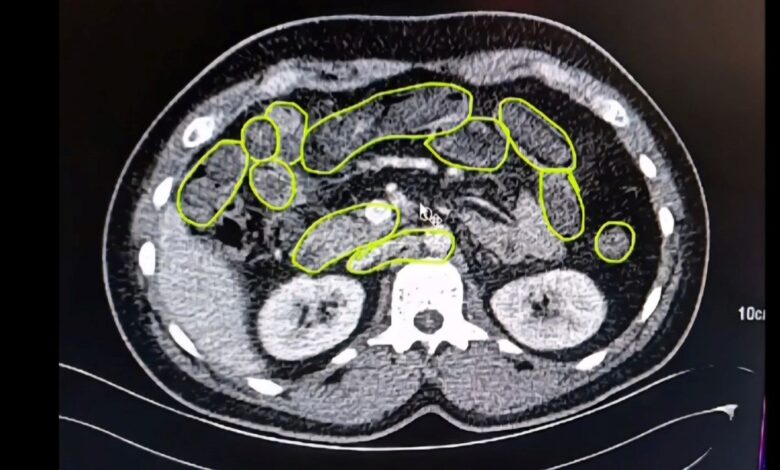

Röntgen ve ultrason sonrası kontrollerde 3 şüphelinin midesinde uyuşturucu madde olduğu belirlendi.

Şüphelilerin yuttukları uyuşturucuları kente sokmaya çalıştıkları tespit edildi. Kapsüller, sağlık ekibinin müdahalesiyle çıkarıldı. Taburcu edilen şüpheliler, İlçe Jandarma Komutanlığı’na götürüldü.